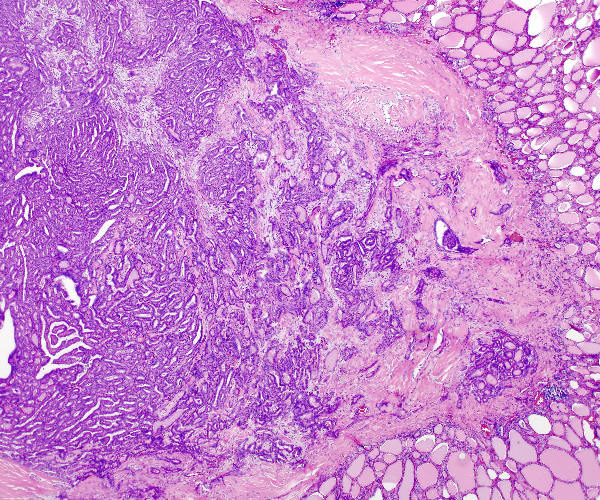

Source: Thyroid_papillary_carcinoma_histopatholgy_(1)